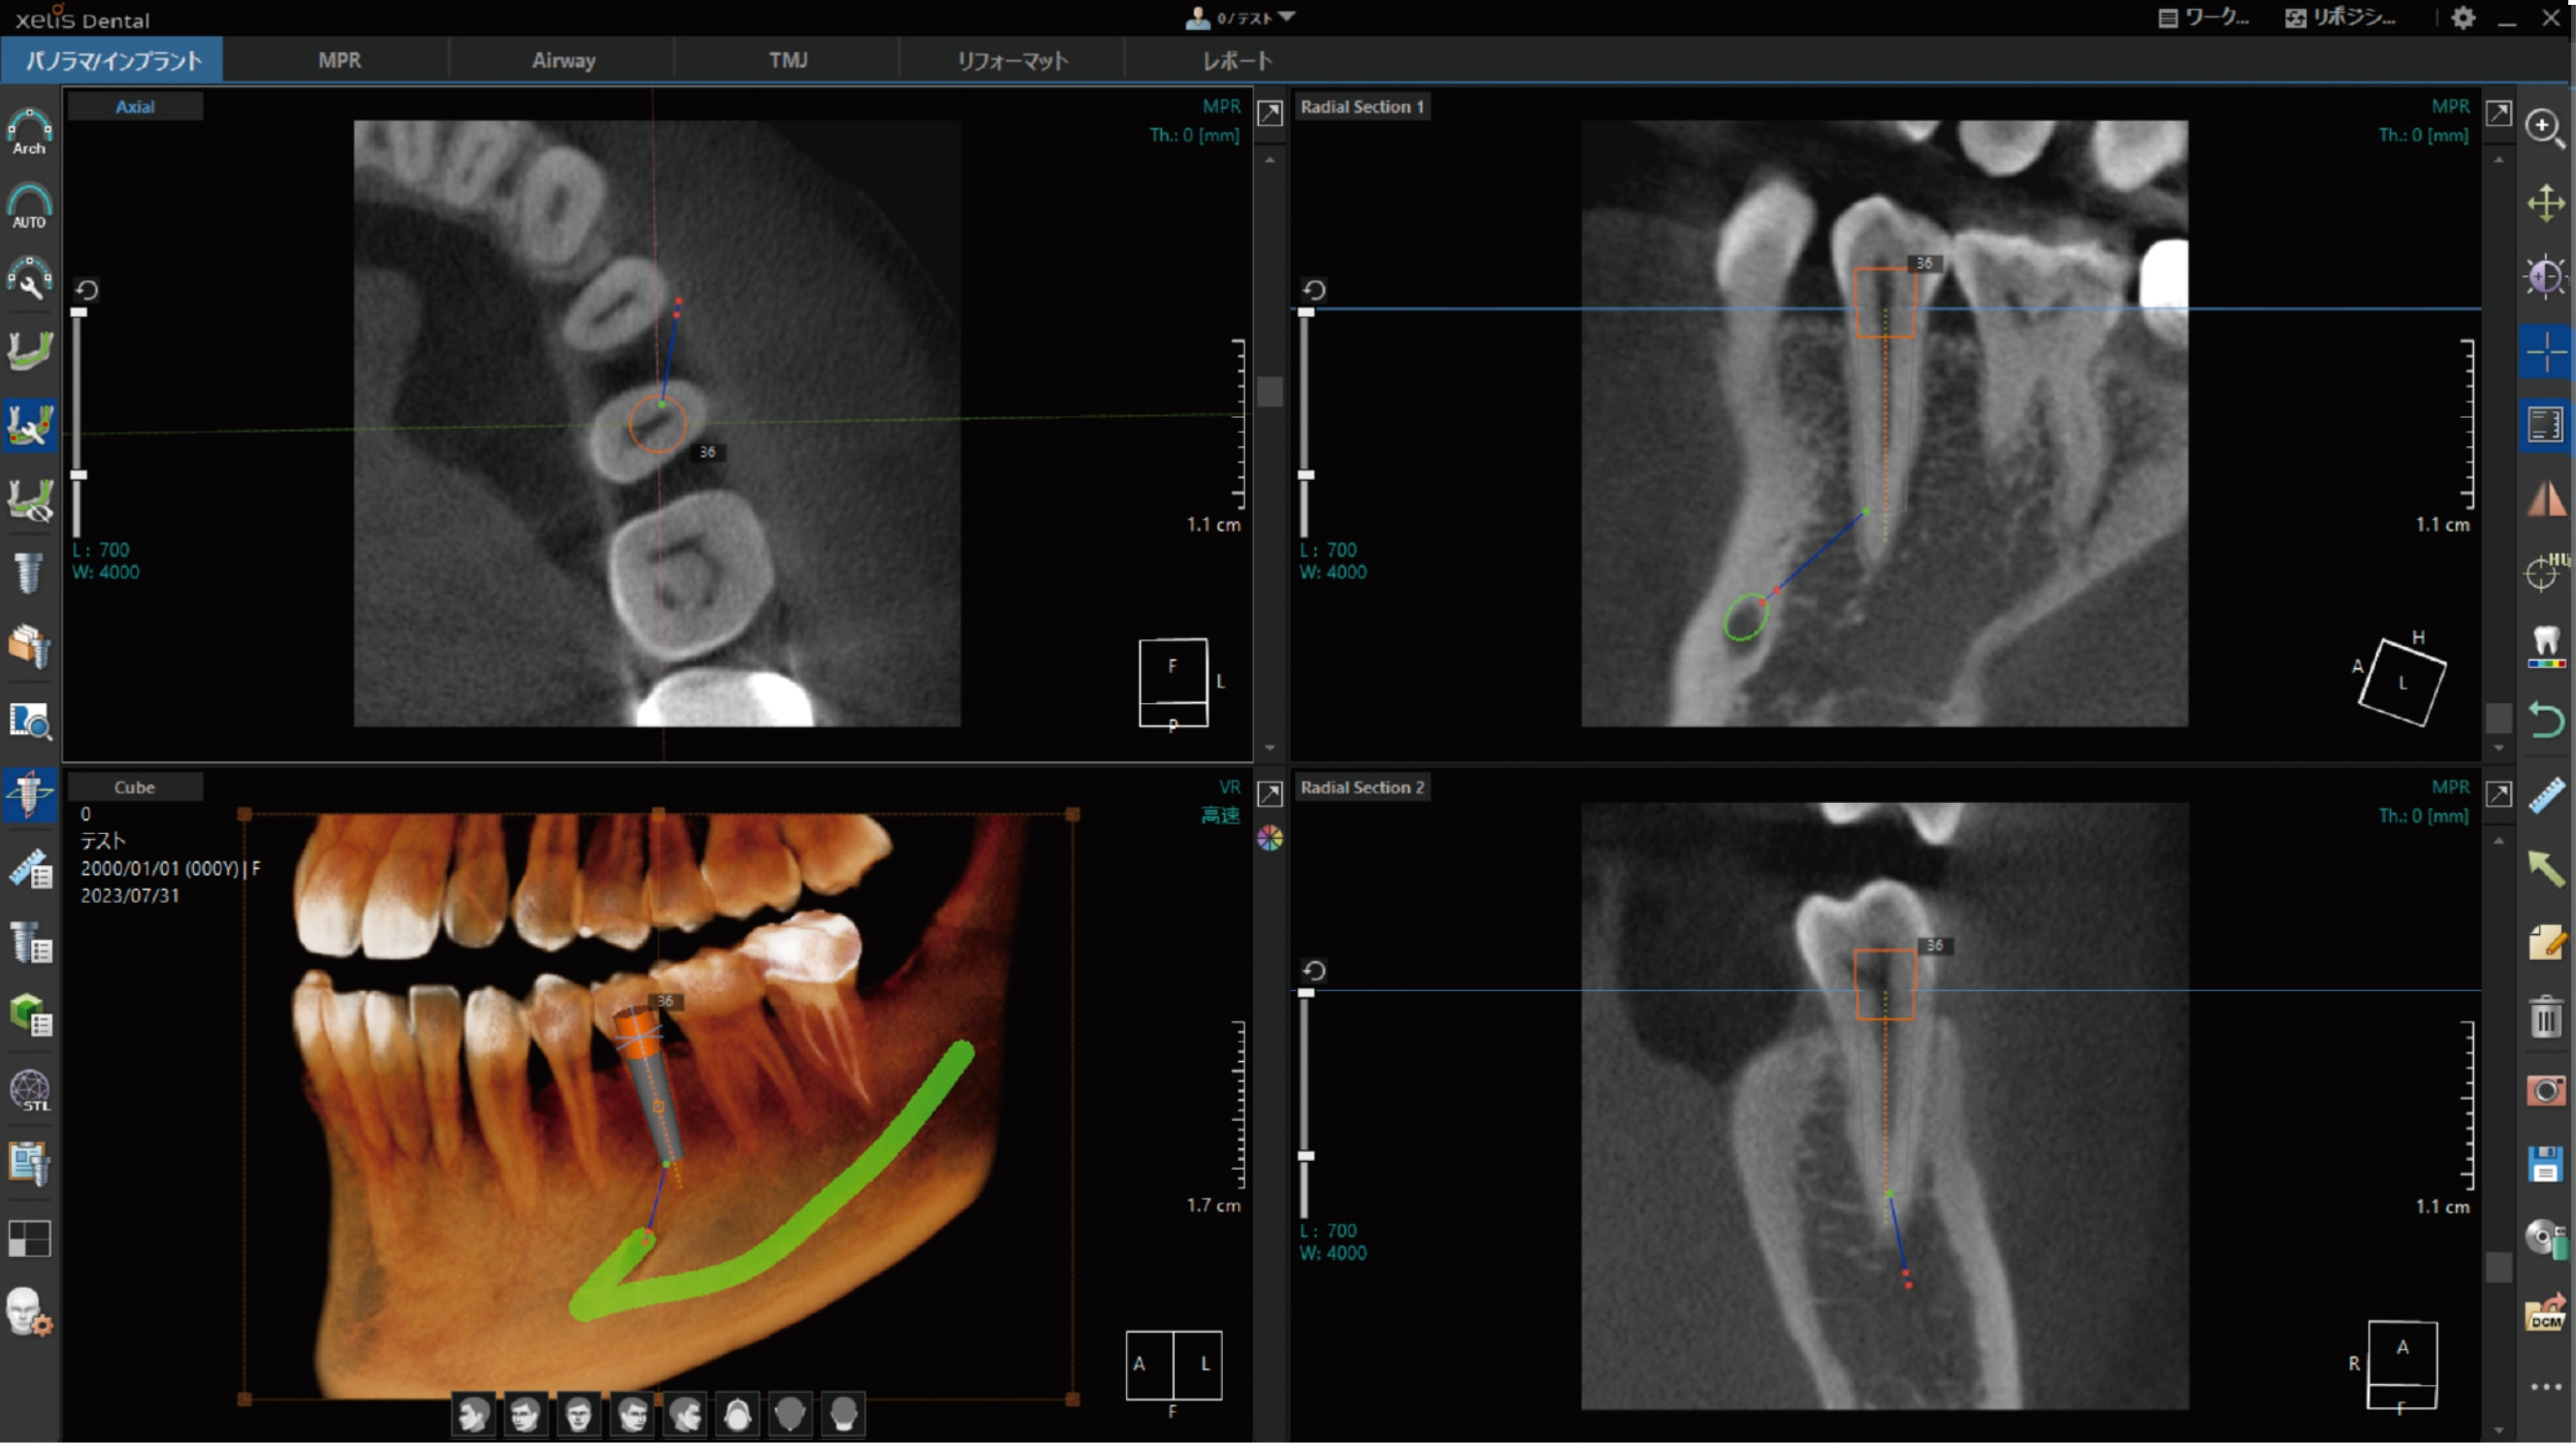

CT画像専用ビューアーソフト「 XelisDental(ゼリスデンタル )」

Pano/Implant、MPR、TMJの各種解析ツールをタブで切替できます。

タブの切替のみで、ツールアイコンが変化する為、迷わず操作が可能です。

VOI , Cube機能 / VRのスカルプト機能

MPR表示では、局所拡大表示も可能。

軸の回転に加え、スライス厚の変更やボリュームレンダリング画像のスカルプト機能も搭載。

VOIやCube機能で、解析部位を絞り込んで表示する事ができます。

歯科領域で必須とされる各解析ツールを搭載。

歯列弓や下顎管の抽出等のアナログな作業を軽減する、各種オート機能を搭載。

オートアーチ機能

任意のアキシャル画像をクリックするだけで、自動的にパノラマ画像が作成できます。

それと同時に、クロスセクショナル画像も作成されます。

下顎管の抽出

下顎孔とオトガイ孔の最小2クリックで、下顎管の抽出が可能です。